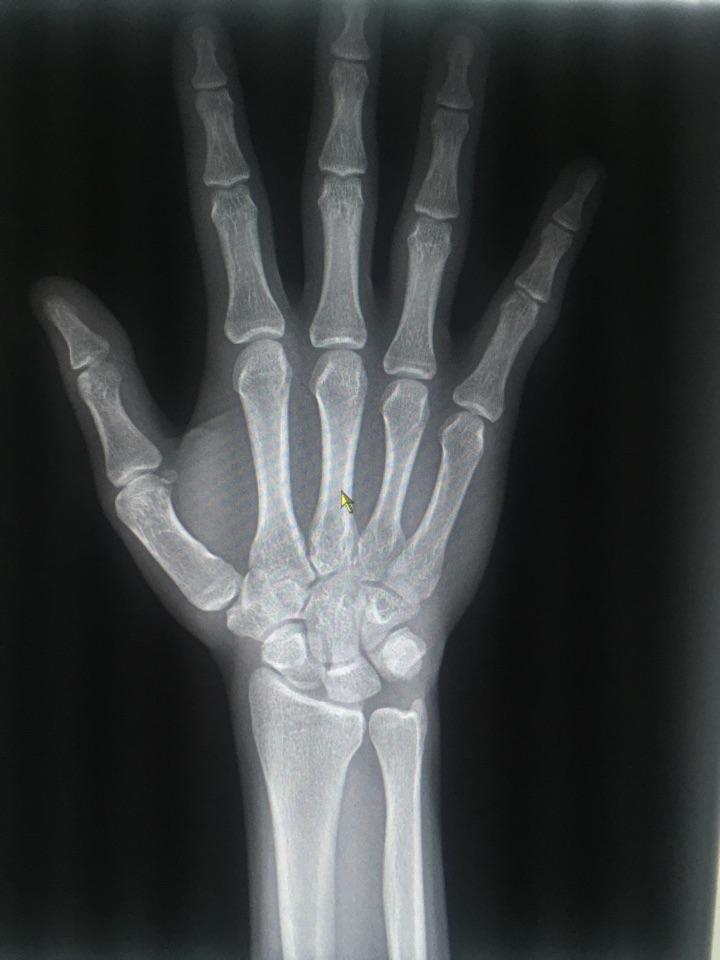

帮忙看下骨骺线闭合了没有,还能不能长高,本人今年15岁

图片尺寸1536x2048